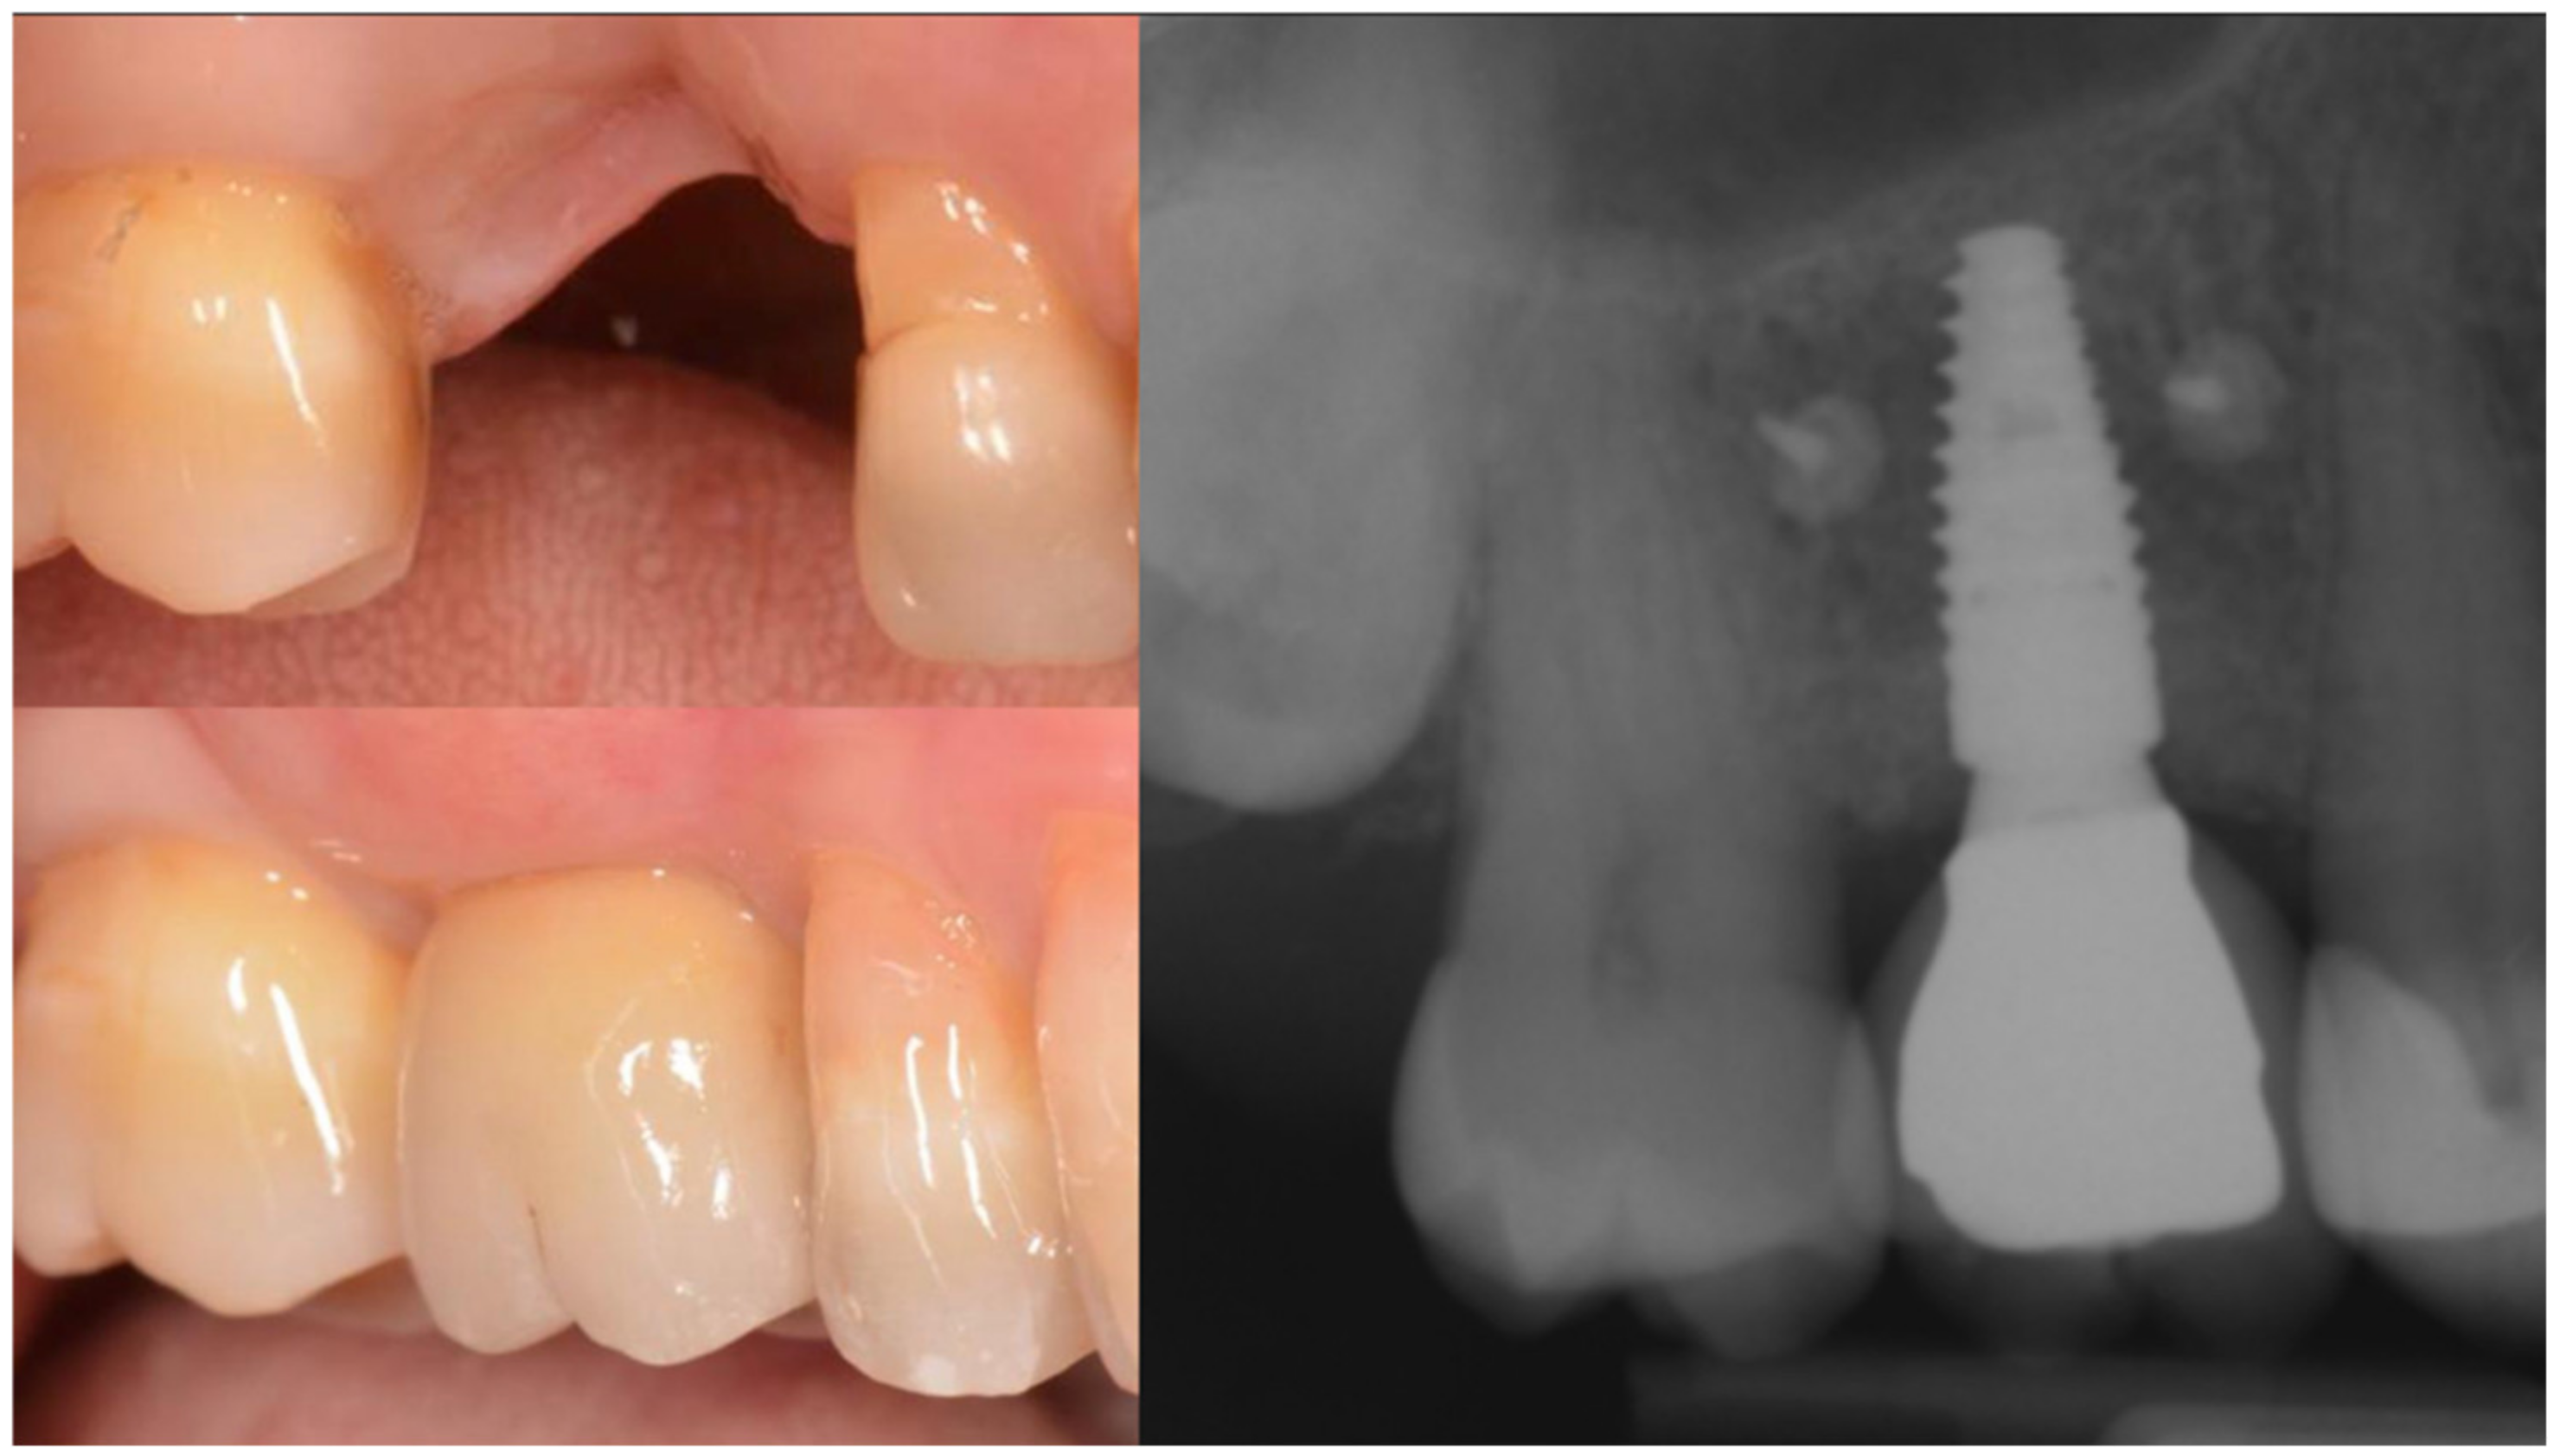

At second stage surgery, a mini-flap was prepared in order to connect healing abutment and protect the papilla; the bone lamina was still in place and it was necessary to drill through it in order to access the implant’s heads (Figure 17 and Figure 18).

Figure 17.

The bone lamina integrated.

Figure 18.

Progression of the case.

More than 3 mm of bone had formed above the implant heads and adjacent to the teeth, and the presence of the interdental papilla after the soft tissue had been conditioned shows proof of it (Figure 19).

Figure 19.

Soft tissue sculpting.

The radiographs at baseline and after completion of the prosthetic restoration also show the GTR effect of GBR in this case on the natural teeth, aside from the expected effect on bone and implants. Both bony peaks to the distal of 11 and mesial of 14 are coronal to the head of the fixture and support interdental papilla (Figure 20 and Figure 21). It is possible to appreciate in the radiographs the stability and good mineralization of the grafted area.

Figure 20.

The supra-crestal component of the bone lamina (blue) and the GTR effect near tooth 11 (white arrow).

Figure 21.

Rx of follow-up completion of restoration (left) and at 3 years after load (right).